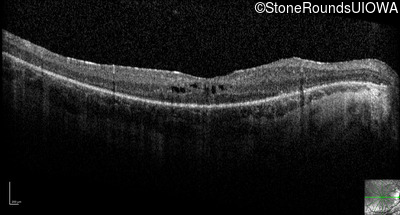

Optical Coherence Tomography - Left - 20/50

Exemplar / OCT Stack